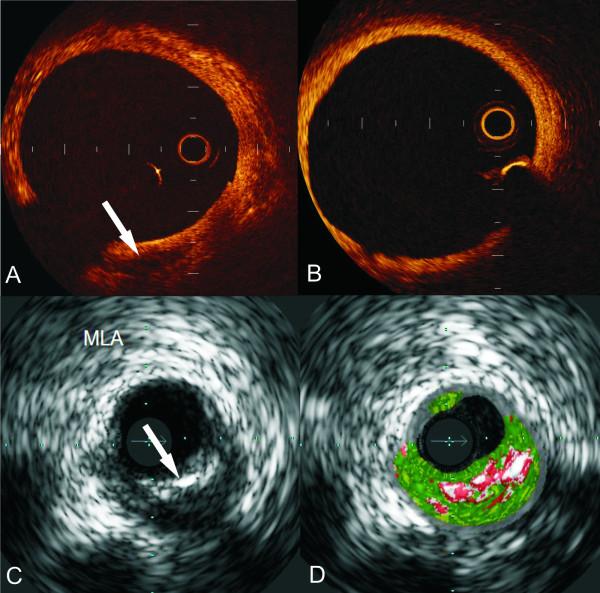

Intravascular ultrasound (IVUS) is an invasive modality which provides cross-sectional images of a coronary artery. In these images both the lumen and outer vessel wall can be identified and accurate estimations of their dimensions and of the plaque burden can be obtained. In addition, further processing of the IVUS backscatter signal helps in the characterization of the type of the plaque and thus it has been used to study the natural history of the atherosclerotic evolution. On the other hand its indigenous limitations do not allow IVUS to assess accurately stent struts coverage, existence of thrombus or exact site of plaque rupture and to identify some of the features associated with increased plaque vulnerability. In order this information to be obtained, other modalities such as optical coherence tomography, angioscopy, near infrared spectroscopy and intravascular magnetic resonance imaging have either been utilized or are under evaluation. The aim of this review article is to present the current utilities of IVUS in research and to discuss its advantages and disadvantages over the other imaging techniques.

血管内超声(IVUS)是一种侵入性检查手段,可提供冠状动脉的横截面图像。在这些图像中,可以识别管腔和血管外壁,并能准确估计它们的尺寸以及斑块负荷。此外,对IVUS背向散射信号的进一步处理有助于斑块类型的特征化,因此它已被用于研究动脉粥样硬化演变的自然史。另一方面,其固有的局限性使得IVUS无法准确评估支架支柱的覆盖情况、血栓的存在或斑块破裂的确切部位,也无法识别一些与斑块易损性增加相关的特征。为了获取这些信息,其他检查手段如光学相干断层扫描、血管镜检查、近红外光谱和血管内磁共振成像已被采用或正在评估中。这篇综述文章的目的是介绍IVUS目前在研究中的应用,并讨论其相对于其他成像技术的优缺点。